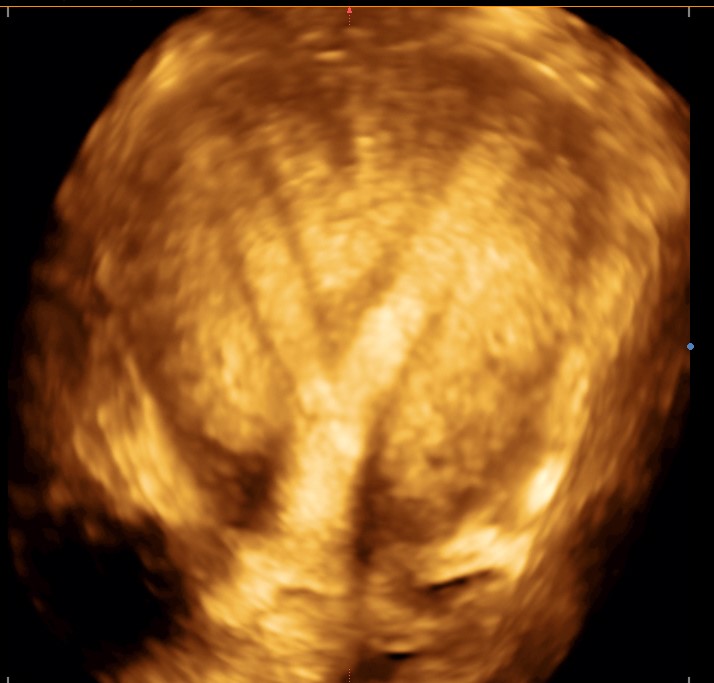

Ultrassonografia transvaginal 3D

Exame realizado via vaginal com o objetivo de avaliar os orgãos genitais internos, esclarecendo melhor determinadas situações como malformações uterinas, posição de miomas, posição do DIU (dispositivo intra-uterino), sinéquias intrauterinas, entre outras indicações.